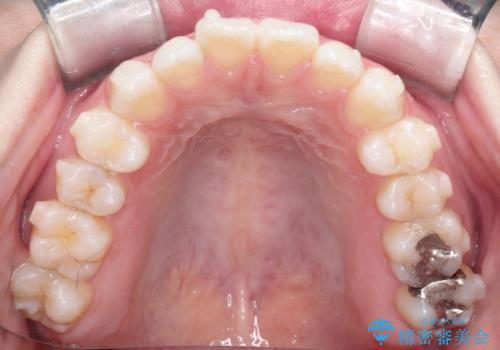

【インビザライン】がたつきをなおしたい

- 上下の前歯の凸凹が気になり、来院されました。

インビザラインで綺麗に仕上がり、満足していただきました。